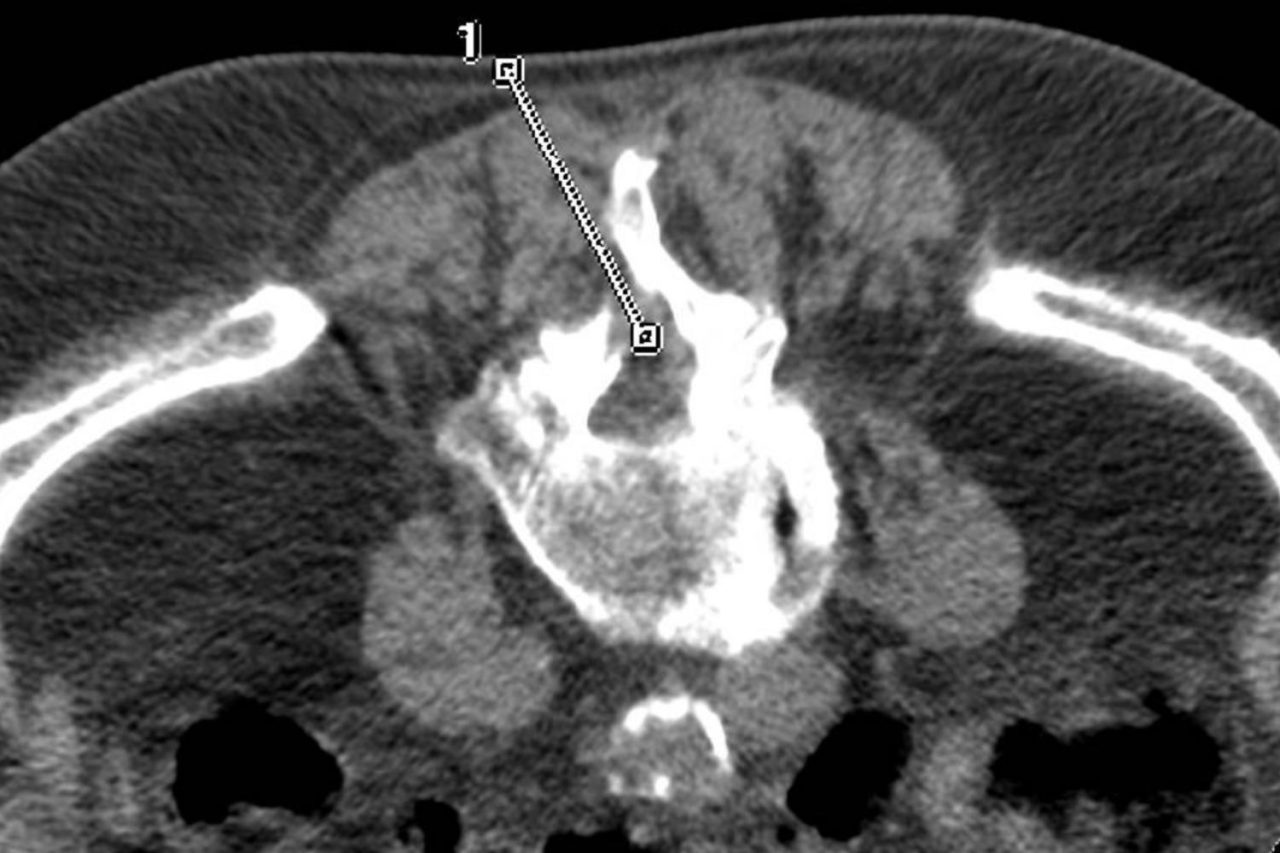

Pour toutes les informations concernant les traitements des sciatiques, lisez cet article : "Que faire en cas de sciatique ?". Figure 3 - Infiltration articulaire postérieure L4- L5 et L5-S1.

Source: newrneteno.pages.dev Infiltrations L4 L5 Entre Avis et Réalités , Figure 3 - Infiltration articulaire postérieure L4- L5 et L5-S1. Découvrez les avis sur les infiltrations sous scanner au niveau L4 L5

Source: cloudlanhom.pages.dev Epidurale Infiltrationen bei Rückenschmerzen Orthopaedie Schmerztherapie , Informez-vous sur les alternatives et faites le choix qui vous correspond le mieux. Figure 3 - Infiltration articulaire postérieure L4- L5 et L5-S1.

Source: likecolabip.pages.dev Infiltration épidurale La Radiologie , Je viens de subir une infiltration épidurale L4 L5 en raison d'une sciatique dont l'origine semble être un canal lombaire étroit combiné à une antélisthésis de L4 sur L5. Figure 3 - Infiltration articulaire postérieure L4- L5 et L5-S1.